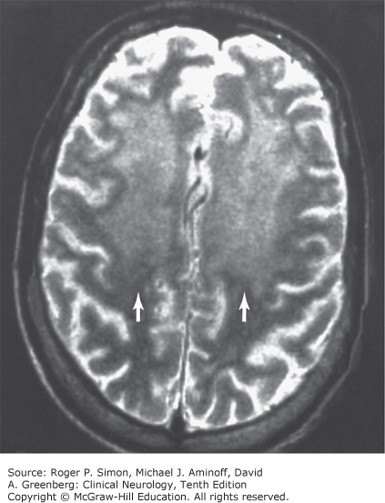

T2-weighted MRI in HIV-associated dementia, showing increased signal intensity (arrows) in subcortical white matter.

Source: Simon RP, Aminoff MJ, Greenberg DA. Clinical Neurology, 10e; 2017.